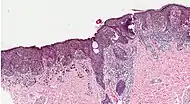

Superficial spreading melanoma Melanoma cells with nest formation along the dermo-epidermal junction. 70%

Nodular melanoma Grows relatively more in depth than in width. 15% - 20%

Lentigo maligna melanoma Linear spread of atypical epidermal melanocytes as well as invasion into the dermis.[78] 5% - 10%

Acral lentiginous melanoma Continuous proliferation of atypical melanocytes at the dermoepidermal junction.[79] 7% - 10%